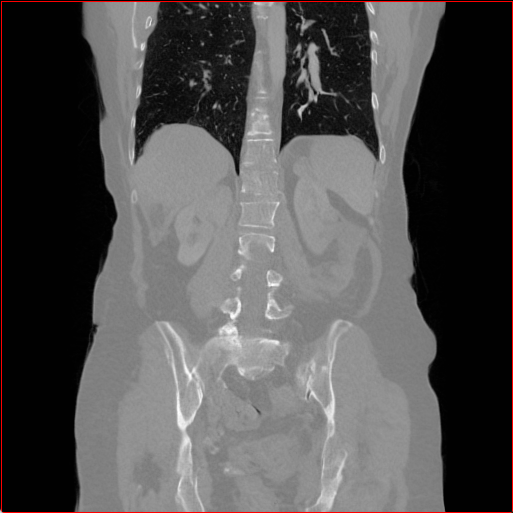

Figure 3 shows the generalizability of MAISI-v2 ControlNet for different body regions and voxel sizes. Figure 4 shows qualitative results for MAISI-v2 ControlNet on 5 types of tumors.

Head Region

1.1×1.1×1.11.1\times 1.1\times 1.1

mm

256×256×256256\times 256\times 256

Chest Region

1×1×11\times 1\times 1

384×384×384384\times 384\times 384

Abdomen Region

1×1×0.71\times 1\times 0.7

512×512×768512\times 512\times 768

Figure 3: MAISI-v2 segmentation-guided results for small to large volume size and three different regions.